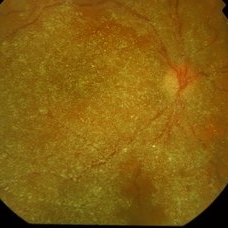

Triamcinolone in vitrectomised eye

Dec 25 2012 by Alex P. Hunyor, MD

Early postoperative fundus photograph of a 52-year-old male following vitrectomy with ERM/ILM peeling and injection of intravitreal triamcinolone. The triamcinolone crystals are diffusely adherent to the posterior pole.

Condition/keywords: triamcinolone